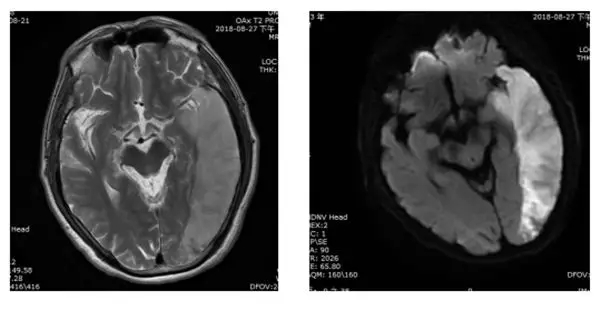

1、颅脑(脑梗死、脑出血、脑肿瘤、脑血管疾病、颅脑外伤等病变)

早期脑梗患者

肿瘤患者